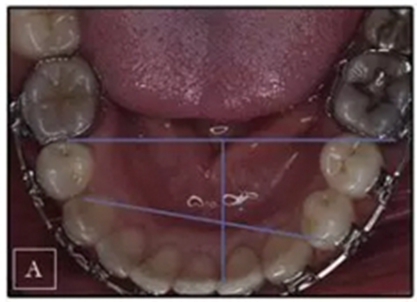

患者是一名39歲的白人婦女,病史不明。她主訴是她的右側(cè)顳下關(guān)節(jié)有不適癥狀,并希望改善她的笑容。她有一個對稱的臉型和一個II類2分類的微笑。她的側(cè)貌是凸的,90°的鼻唇角和骨性下頜骨發(fā)育不足??趦?nèi),上頜中線與面部重合,但下頜中線向右側(cè)偏移5mm;存在6mm的深覆蓋。她的兩側(cè)都是I類磨牙關(guān)系,左側(cè)是I類尖牙關(guān)系,右側(cè)是完全的II類尖牙關(guān)系。下頜右側(cè)第二前磨牙先天性缺失(圖1和圖2)。最初的全景片顯示了足夠的骨質(zhì)水平和全部的第三磨牙(圖3)。治療前的頭影測量片片和相應(yīng)的頭影測量圖(圖3)證實ANB為7°,Wits評估為6 mm的骨性II類錯合(表)。上頜切牙相對與面部和顱底的位置很好。下頜切牙前傾。診斷為II類2分類錯合畸形,伴有骨性下頜發(fā)育不足,右側(cè)顳下頜關(guān)節(jié)癥狀,下頜中線向右側(cè)偏移5mm,先天性右下第二前磨牙缺失。

圖2. 治療前牙齒石膏模型

圖3. 治療前頭影側(cè)位片,頭影測量描跡圖和全口X光片